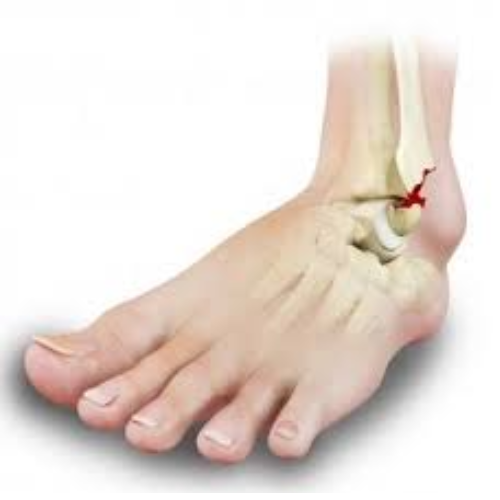

Ankle Fractures

An ankle fracture is a break in one or more bones that make up the ankle joint, usually caused by twisting injuries, falls or accidents. Depending on the severity, it can range from a simple hairline crack to a complex break involving multiple bones and ligaments. Treatment may involve immobilization with a cast or brace, or surgery to realign and stabilize the bones.

Who Needs It?

• Individuals experiencing severe pain, swelling or bruising around the ankle after an injury.

• Patients unable to bear weight or walk properly on the affected foot.

• Those with visible deformity or instability in the ankle joint.

• Patients whose fracture requires surgical intervention for proper healing.

Benefits:

• Relieves pain and reduces swelling.

• Ensures proper bone alignment and healing.

• Restores ankle strength, mobility and stability.

• Prevents long-term complications like arthritis, chronic pain or deformity.